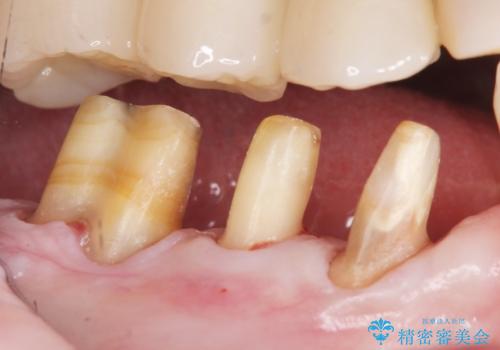

再生療法と骨外科処置により、歯周ポケットは全周2mm以下となりました。

根本的な歯周病の治療を行うことで不安がなくなり、患者様に喜んで頂けました。

奥歯の動揺がなくなりしっかりと咬むことができ、審美的・機能的にもご満足頂けました。

被せ物の種類:オールセラミッククラウン ベレッツァ